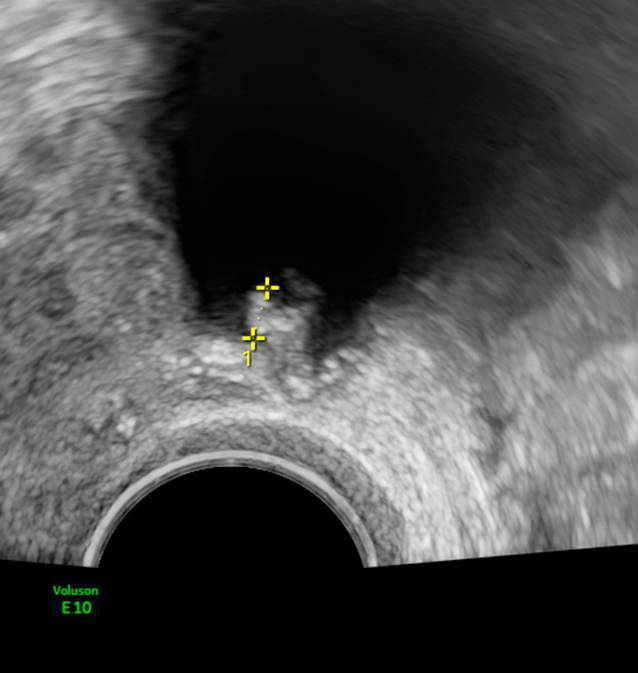

Die „papillary projections“ sind mehr als 3 mm große Vorwölbungen vom Zystenrand ins Zystenlumen (Abb. 6). Die Anzahl dieser Vorwölbungen im Untersuchungsgebiet muss gezählt werden. Sind diese kleiner als 3 mm, so gelten sie als Unregelmäßigkeit der Zystenwand.

Abb. 6

Beispiel für papilläre Projektion. Die gemessene Strecke beträgt 4,4 mm. Es ist wichtig, nur die papilläre Projektion zu messen und nicht auch den Zystenrand